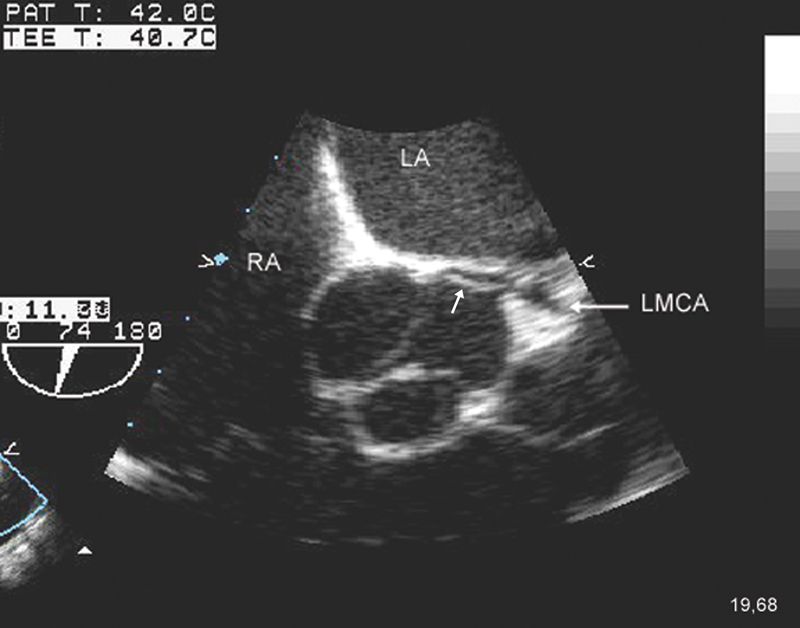

فحوصات تشخيصية لبعض امراض القلب والشرايين التاجية